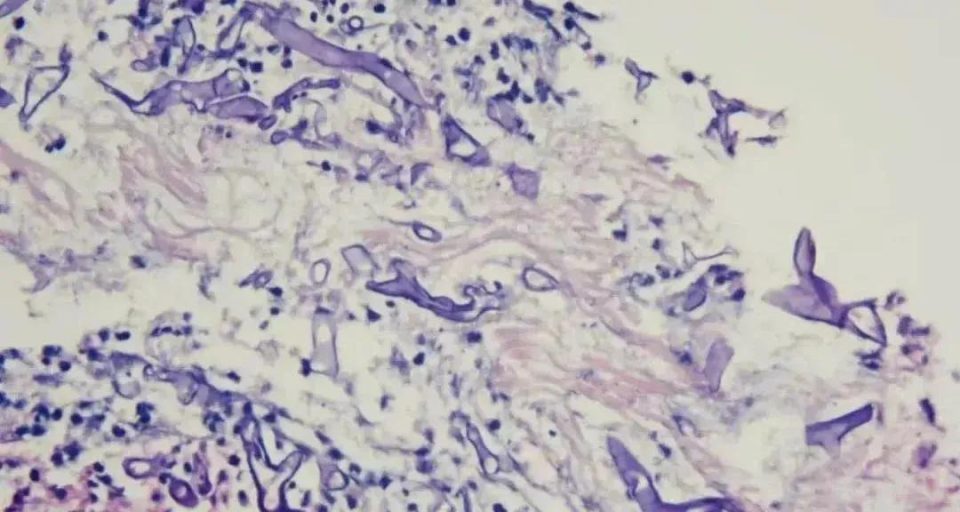

图源:福州晚报,患者病理切片

福建福州的强叔(化名)因反复咳嗽、肺部多发结节就医,曾被怀疑过恶性肿瘤或细菌感染性祸首肺炎,没想到近期终于查出罪魁——毛霉菌。

福州市第一总医院呼吸与危重症医学科主任徐礼裕表示,强叔所患的肺毛霉菌病致死率很高。而让强叔不堪一击的根源,正是他长期失控的血糖。